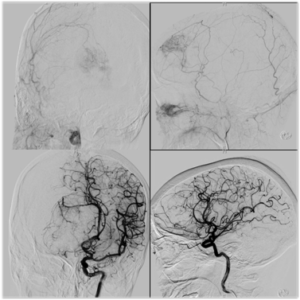

Aneurysm Coiling

Aneurysm coiling refers to the insertion of platinum coils into the aneurysm. A catheter is inserted into a blood vessel and passed using X-ray guidance through the circulation into the brain and then into the aneurysm sac. The microcoils are pushed into the aneurysm through the catheter. Upon depositing within the aneurysm, the coils initiate a thrombotic reaction within the aneurysm. If successful, this prevents further bleeding from the aneurysm.

Balloon Assisted Aneurysm Coiling

Balloon assisted aneurysm coiling is a technique in which a small balloon is inflated within the parent artery of the aneurysm to provide a scaffolding for the coils. This allows for the safe and effective treatment of aneurysm with a broad base (or neck) and with more complex anatomy. a stent may be passed first into the parent artery to serve as a scaffold for the coils.

Stent Assisted Aneurysm Coiling

Stent assisted aneurysm coiling is a technique in which a stent, or tubular piece of mesh, is deposited within the parent artery of the aneurysm to provide a scaffolding for the coils. This allows for the safe and effective treatment of aneurysm with a broad base (or neck) and with more complex anatomy. Placement of an intracranial stent will require administration of anti-platelet drugs, such as aspirin, clopidogrel, or prasugrel.